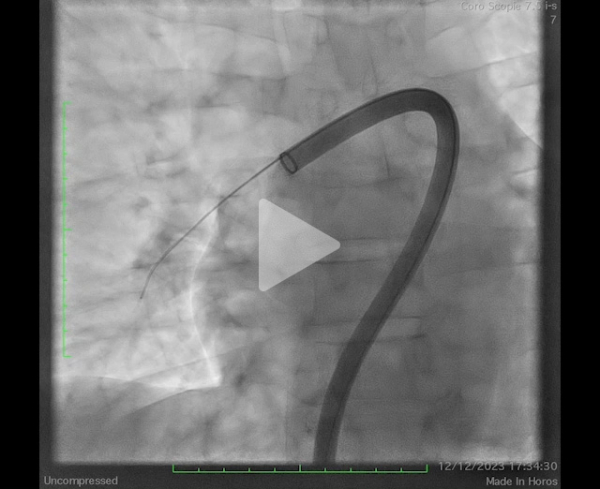

Il s’agit d’une procédure réalisable sous anesthésie locale, par voie fémorale écho-guidée (introducteur de grand diamètre – 24F) et sous monitoring de l’efficacité de l’héparinothérapie. Une cathétérisation sélective des 2 branches de l’artère pulmonaire est réalisée permettant la confirmation d’une hypertension pulmonaire initiale (mesurée à ici à 67mmHg pour la PAPs) (Figure 8), la mise en place d’un cathéter dédié de thromboaspiration permettant de ramener le thrombus (Vidéos 2, 3 et 4). À visée d’épargne sanguine, chaque aspiration est filtrée pour permettre une réinjection du sang.

Vidéo 2 : angiographie initiale

Vidéo 3 : persistance thrombus occlusif troncus antérieur après aspiration

Vidéo 4 : contrôle après aspiration